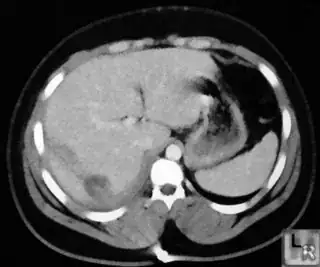

Below are some of the opened and segmented images. Of course there's more to be done in terms of

- separating out the liver region

- generalizing this to a large dataset

but hope this is at least a starting point.